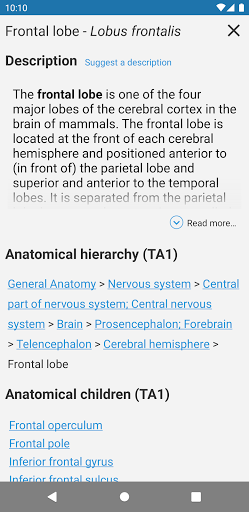

* تقديم الجداول في تعريفات الهياكل التشريحية لتحسين هيكلة البيانات

* تحسين رؤية تعريفات الأجزاء التشريحية

- يتم الآن عرض المصطلحات المتعلقة بالهيكل التشريحي في عرض التفاصيل - تمت إضافة